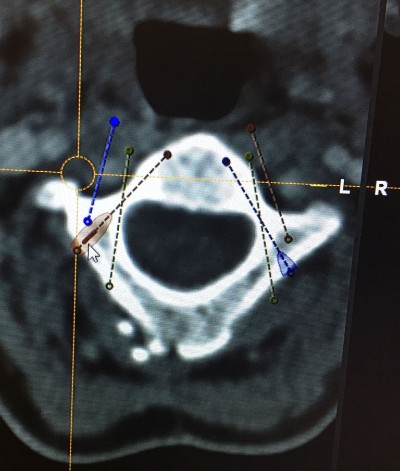

After the preoperative analysis of the Magnetic Resonance Imaging (MRI) and CT scan of each patient, we perform a thin sliced preoperative CT oriented towards neuronavigation that will be carried out during surgery. Prior to surgery we perform a surgical planning of the intraoperative neuronavigation to confirm the trajectories of screws and special anatomical dispositions of structures. It is also important to know and evaluate patients’ concomitant diseases or comorbidities which are frequent in patients affected by Ehler Danlos, such as POTS, Mast Activation Syndrome, cardiac abnormalities … etc. Knowing this it allows to anticipate any possible problems in the postoperative period.

Once in the Operating Room, surgery is performed under general anesthesia, with Neurophysiological monitoring (SSEP – somatosensory evoked potentials), neuronavigation guidance and intraoperative fluoroscopy guidance. Thus we control the spinal cord and nerves (cranial and cervical) in order to avoid potential damages to these important structures. Neuronavigation assistance guides us all through the surgery, thus it diminishes (though it does not eliminate) the risks while placing the screws for the fusion. Both neurophysiological monitoring and neuronavigation guidance are safety measures for the patient.